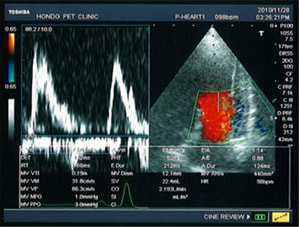

A:超音波カラードップラーでの僧帽弁逆流速度の測定

B:E波とA波の測定

症例:【マルチーズ 12歳齢 去勢オス】

左側胸壁心尖部領域を最強点とするLevine 5/6の収縮期性心雑音が聴取された。

胸部レントゲン検査において重度の心拡大と肺水腫が認められた。超音波検査では、重度の僧帽弁閉鎖不全症、三尖弁閉鎖不全症、中程度の大動脈弁閉鎖不全症を合併していることが判明した。三尖弁逆流速度から肺高血圧症が示唆された。

ACE阻害薬、ピモベンダン、硝酸イソソルビド徐放剤、ベラプロストナトリウム、利尿剤としてフロセミドとスピロノラクトンを用いて治療を行った。